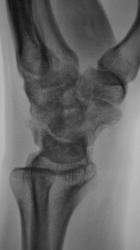

Катенёв Валенти... Дата публикации 13.10.2009, 18:16 Пациент направлен в рентгеновский кабинет хирургом для рентгенографии лучезапястного сустава. Травма. Произведено исследование. pp.1..JPG pp.2..JPG pp.3..JPG pp.4..JPG Ваше мнение коллеги? ВложениеРазмер pp.1..JPG62.4 КБ pp.2..JPG53.6 КБ pp.3..JPG95.92 КБ pp.4..JPG80.54 КБ Втр, 13/10/2009 - 21:14 #1 flagman Не на сайте Был на сайте: 11 лет 5 месяцев назад Зарегистрирован: 05.06.2008 - 20:08 Публикации: 83 странная ладья - неужели перелом? Втр, 13/10/2009 - 21:18 #2 Катенёв Валенти... Не на сайте Был на сайте: 7 лет 3 недели назад Зарегистрирован: 22.03.2008 - 22:15 Публикации: 54876 Один перелом "ладьи"? Втр, 13/10/2009 - 21:29 #3 Павел Владимирович Не на сайте Был на сайте: 16 лет 2 месяцев назад Зарегистрирован: 07.10.2009 - 20:47 Публикации: 11 перелом ладьевидной кости с расхождением отломков Втр, 13/10/2009 - 21:41 #4 Наталия Не на сайте Был на сайте: 8 лет 7 месяцев назад Зарегистрирован: 30.07.2008 - 13:24 Публикации: 538 Двойной перелом ладьевидной кости. Ср, 14/10/2009 - 07:52 #5 v1tal Не на сайте Был на сайте: 4 года 9 месяцев назад Зарегистрирован: 07.06.2008 - 19:41 Публикации: 1779 А как же полулунная ????? Ещё и ладья в предачу. "Знаешь, у некоторых врачей есть комплекс мессии — им необходимо спасать мир. А у тебя комплекс Рубика — тебе необходимо решать головоломки." Ср, 14/10/2009 - 14:38 #6 OPEXOB Не на сайте Был на сайте: 9 лет 11 месяцев назад Зарегистрирован: 26.07.2008 - 10:02 Публикации: 280 Может "снайперы" укажите стрелками, кто, что видет? Ср, 14/10/2009 - 19:48 #7 Глазков Игорь А... Не на сайте Был на сайте: 9 месяцев 2 недели назад Зарегистрирован: 19.12.2008 - 20:41 Публикации: 1597 ладьевидной кости Прийди к Себе

странная ладья - неужели перелом?

Один перелом "ладьи"?

перелом ладьевидной кости с расхождением отломков

Двойной перелом ладьевидной кости.

А как же полулунная ????? Ещё и ладья в предачу.